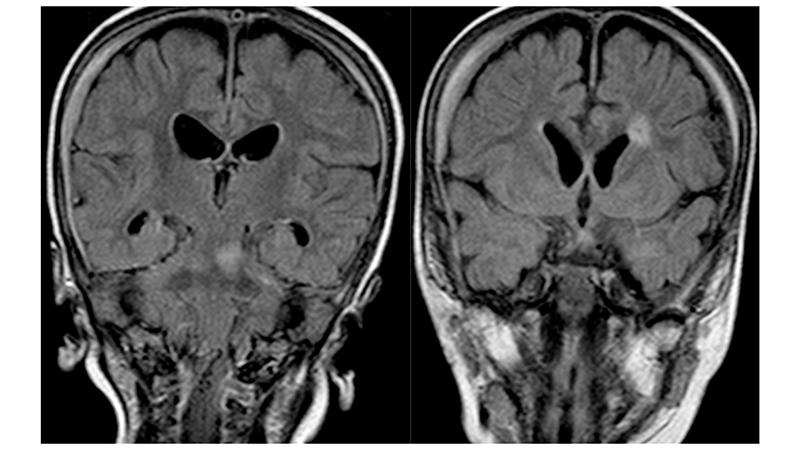

- Στην μαγνητική αγγειογραφία βλέπουμε υποσκληρίδιο αιμάτωμα στο δρέπανο

- και οπισθιοπλάγιους τροφοφόρους κλάδους από τις οπίσθιες εγκεφαλικές αρτηρίες.

- Πρόσφατη μαγνητική τομογραφία δείχνει αναστροφή των ισχαιμικών αλλοιώσεων του εγκεφαλικού στελέχους, αποκατάσταση του κοιλιακού συστήματος με ήπια υποεπενδυματική και φοιώδη ατροφία και πλήρη εξάλειψη των υποσκληριδίων συλλογών.